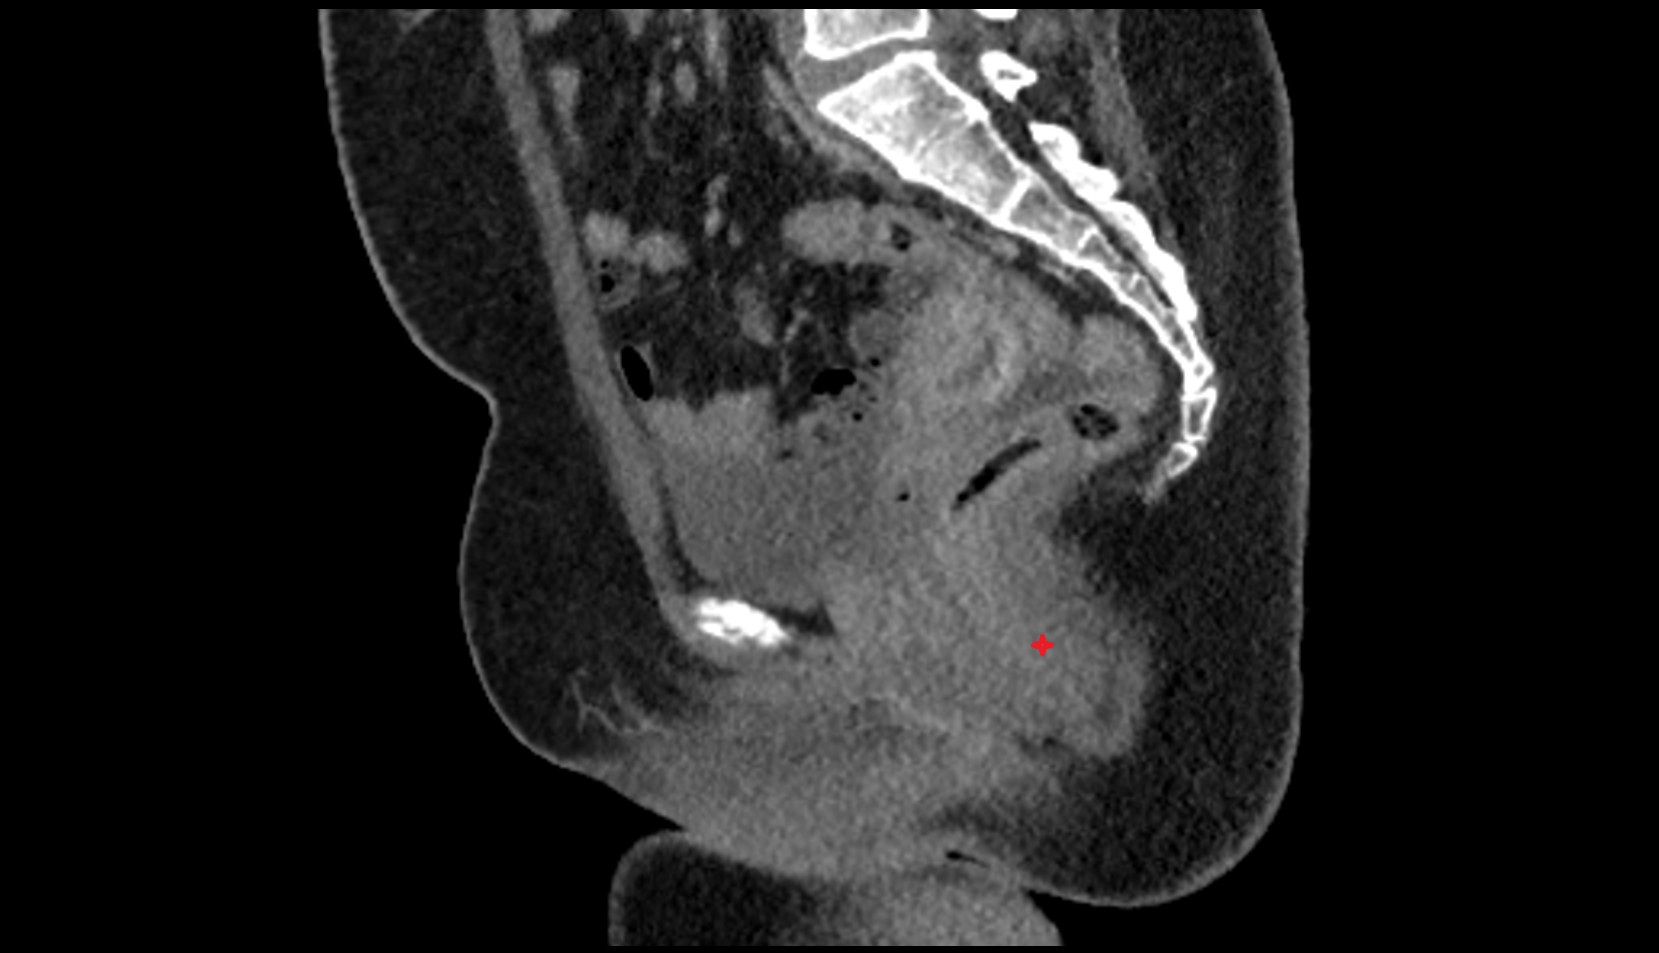

- Placenta

- Uterus (pregnancy)

- Amniotic fluid

- Umbilical cord

- Urinary Bladder in Pregnancy

- Cervix in Pregnancy

- Vagina in Pregnancy

- Fundus of uterus in pregnancy